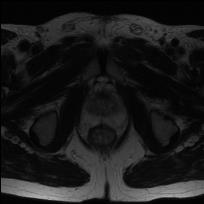

Modern deep neural networks struggle to transfer knowledge and generalize across diverse domains when deployed to real-world applications. Currently, domain generalization (DG) is introduced to learn a universal representation from multiple domains to improve the network generalization ability on unseen domains. However, previous DG methods only focus on the data-level consistency scheme without considering the synergistic regularization among different consistency schemes. In this paper, we present a novel Hierarchical Consistency framework for Domain Generalization (HCDG) by integrating Extrinsic Consistency and Intrinsic Consistency synergistically. Particularly, for the Extrinsic Consistency, we leverage the knowledge across multiple source domains to enforce data-level consistency. To better enhance such consistency, we design a novel Amplitude Gaussian-mixing strategy into Fourier-based data augmentation called DomainUp. For the Intrinsic Consistency, we perform task-level consistency for the same instance under the dual-task scenario. We evaluate the proposed HCDG framework on two medical image segmentation tasks, i.e., optic cup/disc segmentation on fundus images and prostate MRI segmentation. Extensive experimental results manifest the effectiveness and versatility of our HCDG framework.